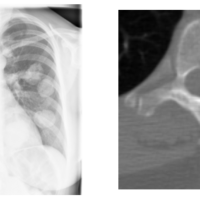

DICOMを使いこなして医療画像を扱う

こんにちは、AI・機械学習チームの浮田 (id:uKita) です。今回は、医療画像においてスタンダードとなっているDICOMという規格について紹介します。 私たちのチームでは臨床現場で活用できるAIの開発に取り組んでおり、様々な医療画像を扱っています。中でもX線やCTなどの放射線画像ではDICOMという形式がメジャーですが、D…